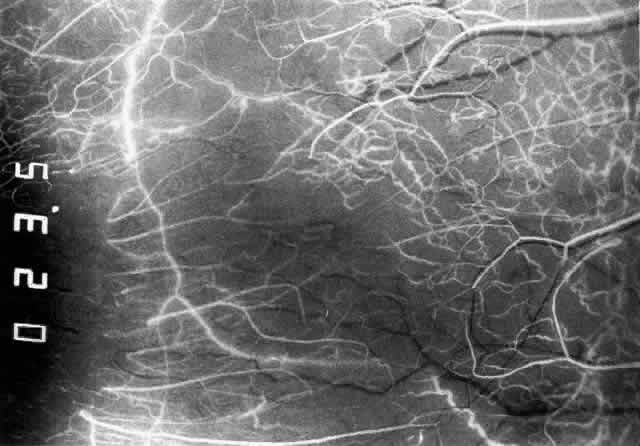

With the increasing use of anterior segment fluorescein angiography in the early detection of severe necrotizing disease of the sclera, it is necessary to have an understanding of the normal anatomy of the vasculature of the anterior segment of the eye.3–5 The blood supply to this region is enormous, being derived from the anterior ciliary arteries, but with extensive collateral arterial anastomoses to the posterior ciliary arteries at the root of the iris (Fig. 1). The anterior system is readily visible with the slit lamp and by anterior segment fluorescein angiography, especially if the eye is inflamed, and its recognition is of vital importance in the differentiation of episcleral and scleral conditions. The separation and displacement of these vascular layers give the most important clinical clues to the site and, hence, the severity of the inflammation. On slit lamp examination, three layers of vessels are readily visible. The conjunctival plexus, which is the most superficial layer of vessels, can be moved over the underlying structures. The superficial episcleral capillary plexus (Fig. 2) is a radially arranged series of vessels lying within the parietal layer of Tenon's capsule. The vessels in this layer anastomose at the limbus with the conjunctival vessels, with other members of the same plexus, and with the deep plexus. The deep episcleral capillary network (see Fig. 2) is closely applied to the sclera in the visceral layer of Tenon's capsule. The vessels anastomose freely with each other, forming a syncytium. The large vessels to and from the intrascleral plexus traverse the episclera near the insertions of the muscles. The conjunctival and superficial episcleral vessels can be blanched with 1:1000 epinephrine or 10% phenylephrine, but the deep vessels are affected slightly. This is of considerable assistance when attempting to differentiate deep and superficial inflammation.

Fig. 3. Normal superior anterior segment angiography in a 35-year-old man. The main anterior ciliary arteries have filled, branching at or adjacent to the limbus to fill the limbal arcade, the recurrent branches of which are passing backward to fill the episcleral and conjunctival vessels. The episcleral circle here is superficial, and the anastomotic vessels are readily visible. There is a close resemblance to the vascular pattern in Figure 1, including the penetrating vessels adjacent to the limbus.

Fig. 4. Normal temporal angiogram of a 32-year-old woman. Fluorescein first enters the anterior ciliary artery above (as in Figure 3), filling the limbal arcade, and then dips deep into the sclera adjacent to the limbus; it can just be distinguished in the deep scleral tissue adjacent to the limbus. The posterior tarsal circulation can be seen filling at the same stage.

Fig. 5. Normal temporal angiogram in the same 32-year-old woman as in Figure 3 two seconds later. The superficial episcleral vessels are filling from a superficial branch of the anterior ciliary artery; the deep circle is now difficult to define but can be seen contributing to the iris vascular filling. The limbal arcade and conjunctiva near the limbus are filled from the superficial branches. Both the episcleral plexus and the conjunctival plexuses perfuse late, about 3 mm from the limbus. This watershed zone is important in the etiology of scleral disease.

Fig. 6. Normal left temporal angiogram of a 33-year-old man. In this angiogram the anterior conjunctival vessels and episcleral vessels are derived from the main ciliary artery trunk at the limbus, filling simultaneously with the iris vessels at a very early stage of the angiogram.